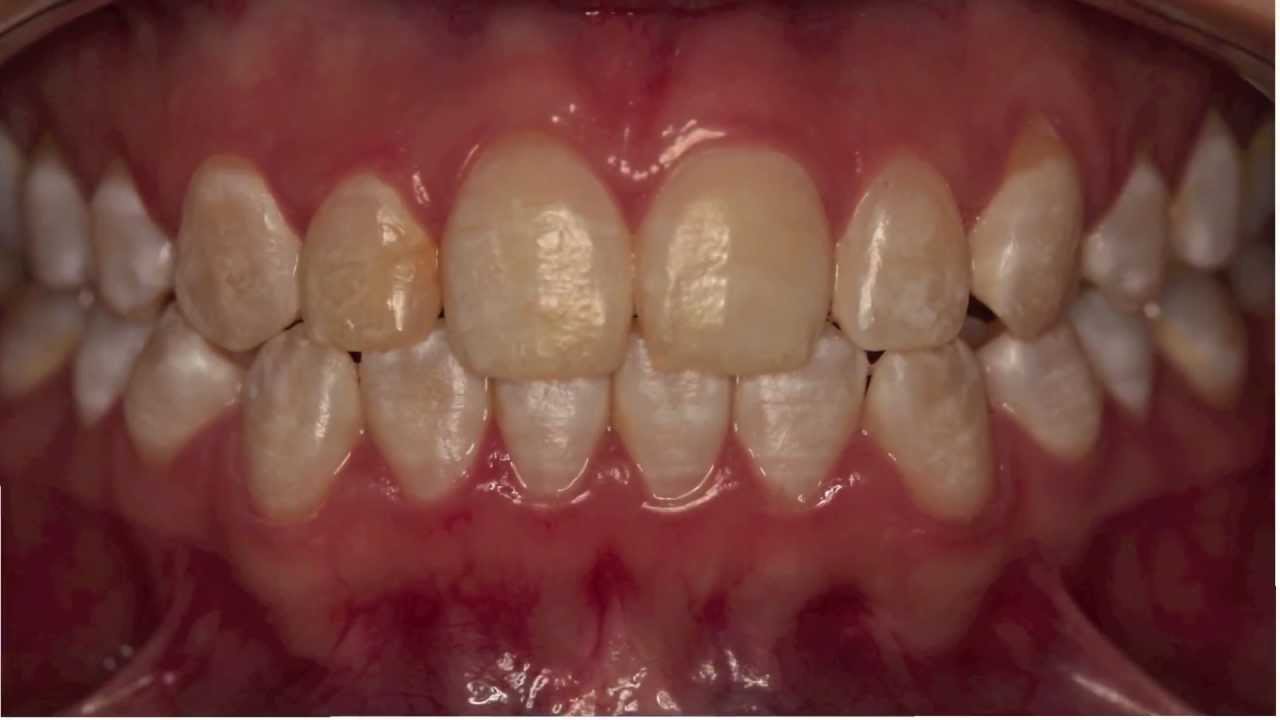

На фотографии зубы,пораженные кариесом начального этапа – белый кариес, когда на зубной эмали видны матовые белые пятна.

Первоначальным этапом кариеса на стадии пятна принято считать состояние белого кариеса. Заболевание отличается появлением матовых белых пятен по всей поверхности зубной эмали. Врач может наблюдать формирование массивных отложений и легкого зубного налета. Это свидетельствует о проведении неполноценных гигиенических процедур в ротовой полости пациента.